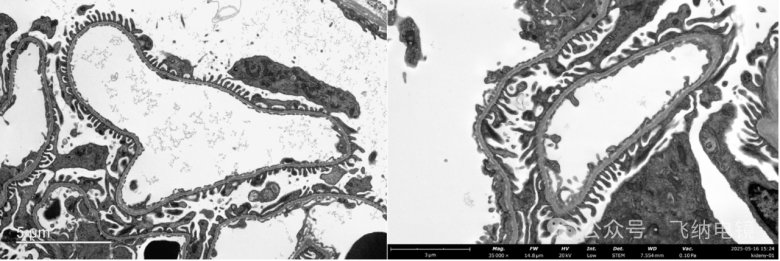

03組織切片——鼻粘膜上皮細(xì)胞

左:TEM;右:Pharos STEM